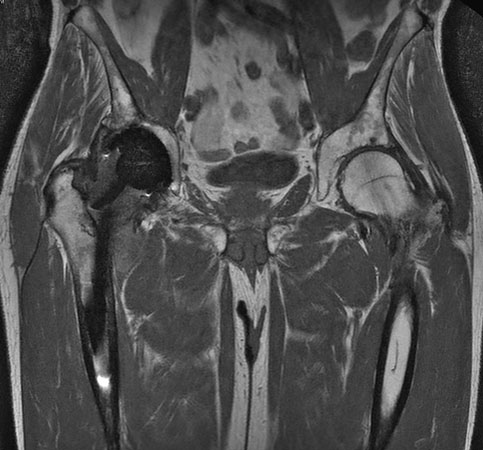

Hip imaging with metal implant using MARS at 1.5T

**Only for use with MR Safe or MR Conditional Implants by strictly following the Instructions for Use.